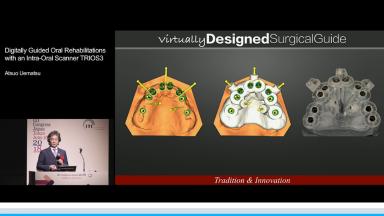

Digitally Guided Oral Rehabilitations with an Intra-Oral Scanner TRIOS3

光学印象による変形の少ない無圧印象とCTによる硬組織のデータにより補綴主導の治療計画を立案し、状況に応じて外科的侵襲の少ない方法を選択することで患者負担の軽減と治療期間の短縮が図られる。インプラントを用いて咬合再構成を行う場合にデジタル技術により仮想的な基準を可視化することで精度の高い診療が可能となる。この講演では咬合再構成をデジタル技術により行った症例を提示している。

デジタル技術による咬合再構成を行った臨床例について知る